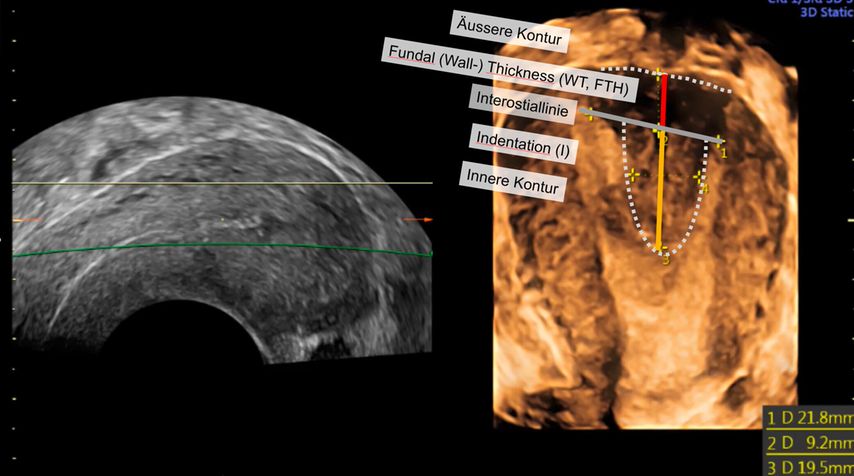

Die Untersuchung wird idealerweise bei hoch aufgebautem Endometrium durchgeführt. Nach Erstellung der Koronarebene kann sowohl die äussere als auch die innere Uteruskontur dargestellt und die Fundusdicke («fundal thickness», FTH) bestimmt werden (Abb. 2). Eine allfällige Septierung ist dabei einfach erkennbar und mittels eines Messkreuzes leicht objektivierbar. Dies lässt sich einfach konstruieren: Zunächst wird eine Hilfslinie zwischen den beiden inneren Tubenostien eingezeichnet (sog. Interostiallinie). Nun kann kranial davon die Fundusdicke (bis zur Serosa) und kaudal davon die Länge des Septums sowie der Winkel der Septumspitze bzw. Carina ausgemessen werden (Abb. 3). Je nach Klassifikationssystem unterscheiden sich hier die Definitionen bzw. Massangaben, welche zur Diagnose einer Fehlbildung nötig sind. Während die ESHRE-ESGE-Guideline relativ «laxe» Kriterien vorschlägt, unter deren Anwendung viele Patientinnen die Diagnose eines Uterus (sub-)septus erhalten würden (bis zu 80%!), landen gemäss ASRM-Klassifikation viele Patientinnen in einer «Grauzone». Hier bewähren sich die CUME-Kriterien, mit deren Hilfe eine Einteilung gelingt, die am ehesten der tatsächlichen Prävalenz entspricht, und dies bei entsprechender Trennschärfe.8 Die vorgeschlagenen Kriterien zur Diagnose eines Uterusseptums sind eine Septumlänge von mindestens 10 mm, ein Winkel von <140° und ein Verhältnis Septum:Fundusdicke von >110% (Abb. 4, Tab. 1).

Abb. 3: Ausmessen der Septumlänge. Nach Anlegen der Interostiallinie (grau) zwischen den Tubenostien können die Fundusdicke und das Septum (innere Einkerbung, engl. «indentation») ausgemessen werden. Nicht eingezeichnet ist hier die Messung des Septumwinkels

Abb. 4: Kriterien zur Definition eines Uterus subseptus gemäss verschiedenen Klassifikationssystemen. I: «indentation» (Septum), WT: «wall thickness» (Fundusdicke)